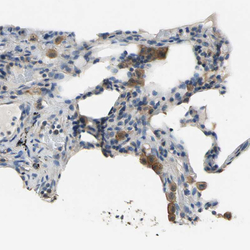

- Experimental details

- Immunohistochemical staining of human lung shows moderate cytoplasmic positivity in macrophages.

- Sample type

- HUMAN